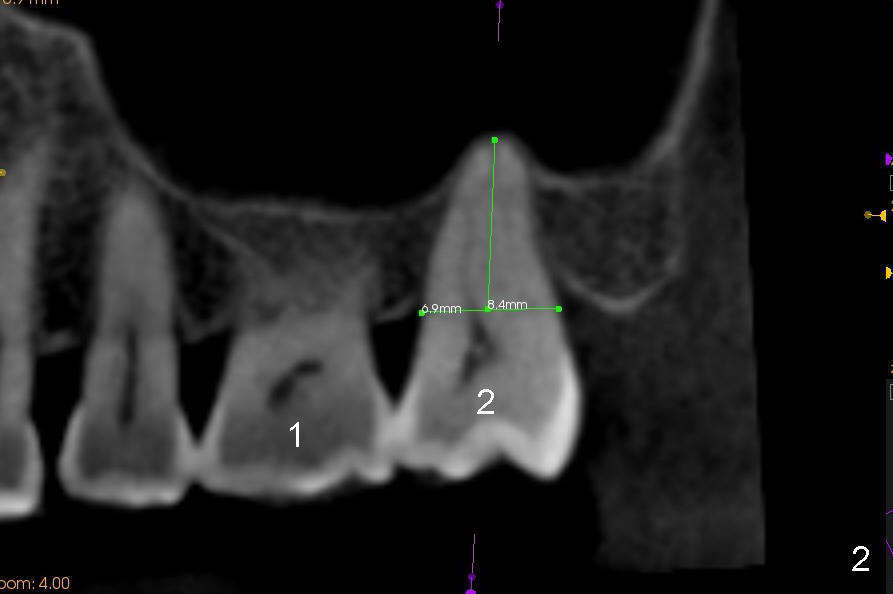

When the buccal roots are fused, there are 3 potential sites for immediate implant (Fig.1'): septum (*), buccal (B) and palatal (P) sockets. Septal placement (6.9x8 mm bone level implant) is the most ideal for restoration (Fig.3). The length of the implant can be increased (10 mm) with sinus lift so that the base of the implant between the buccal and palatal apices in height (Fig.4). Primary stability is derived mainly from the implant body engagement into the septum (Fig.5 coronal section through the septum). If bone density in the septum is high, a small implant may be appropriate (Fig.6,7: 6.4x8 mm). The large implant (6.9 mm) is chosen so that amount of bone graft to be used (Fig.8 red circles) is less.